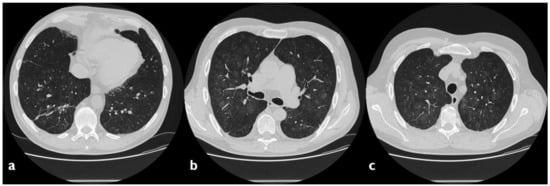

| HRCT Pattern | Associated Drugs |

|---|---|

| Fibrotic pattern | Nitrofurantoin (chronic toxicity), methotrexate, sulfalazina, rituximab, tocilizumab, bleomycin, busulfan, cyclophosphamide (chronic toxicity), amiodarone (form with fibrous course), tocainide, cocaine |

| Organizing pneumonia | Nitrofurantoin (chronic toxicity), methotrexate |

| Mosaic pattern | Nitrofurantoin (acute toxicity), methotrexate, sulfalazina |

| Isolated ground glass | Rituximab, tocilizumab, cyclophosphamide (acute reaction), amiodarone (initial stage), cocaine |

| Alveolar hemorrhage | Penicillamine, rituximab, cocaine |

| Pulmonary edema | Acetyl-salicylic acid, mitomycin |

| Pleural effusion | Sulfonamides, methotrexate |